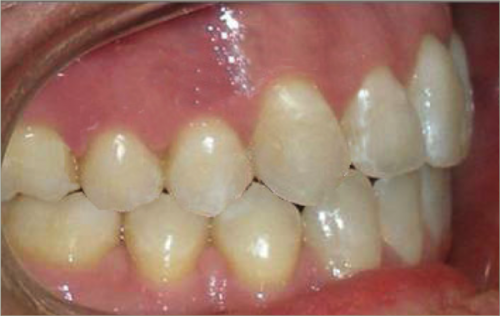

30 year old male:

Diagnosis:

- Upper and lower crowding

- Narrow upper & lowerarch forms

- Open bite

Treatment:

- Invisalign

- Non-Extraction

- 27 months